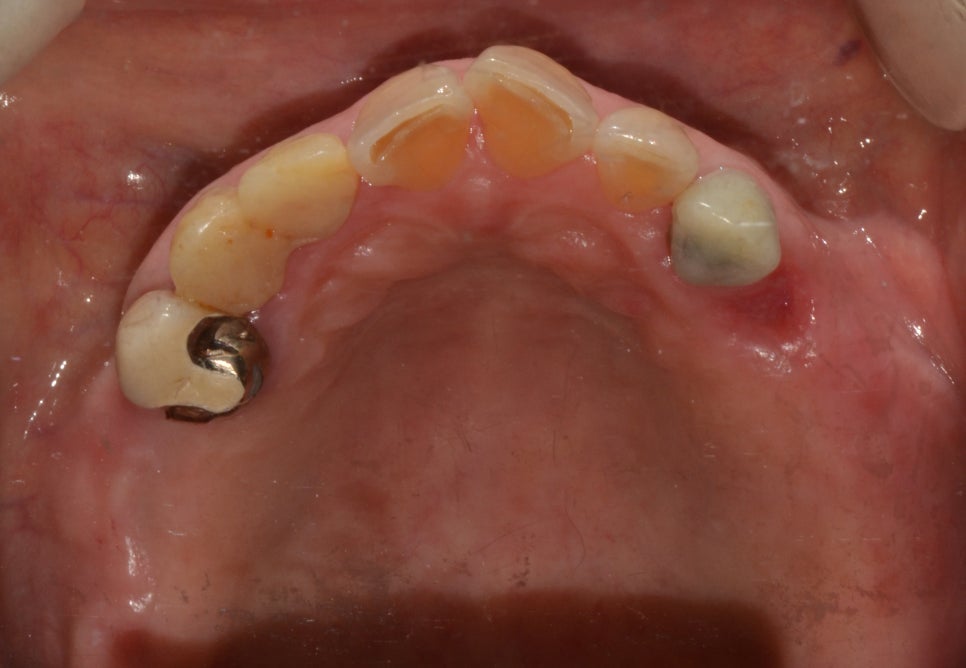

치료 전

2018년 8월 22일 (1년 4개월)

내원 이유

60대 여성분이셨으며 상실된 치아들을 틀니로 해결을 해주셨다가 불편함을 느끼고 임플란트 치료를 원하셨습니다. 임플란트는 식립을 진행하고 난 후에 편하면서 오래 잘 사용할 수 있는 방법이었는데요. 저작력이 기존에 있는 치아와 비슷하여 음식을 씹는 힘도 잘 내어주어 식사를 잘 하실 수 있으며 외관상 보이는 부분도 주변에 있는 치아와 유사하게 보철물이 만들어졌기 때문에 인공적으로 만든 치아라는 것이 티가 나지 않아 사용을 하시기에도 불편함이 없었습니다.